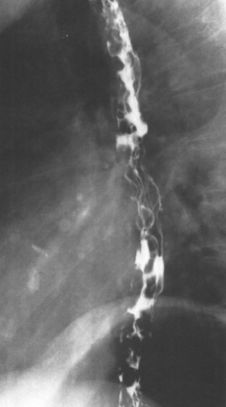

食管痉挛:螺旋状、波浪形。

食管痉挛:螺旋状、波浪状